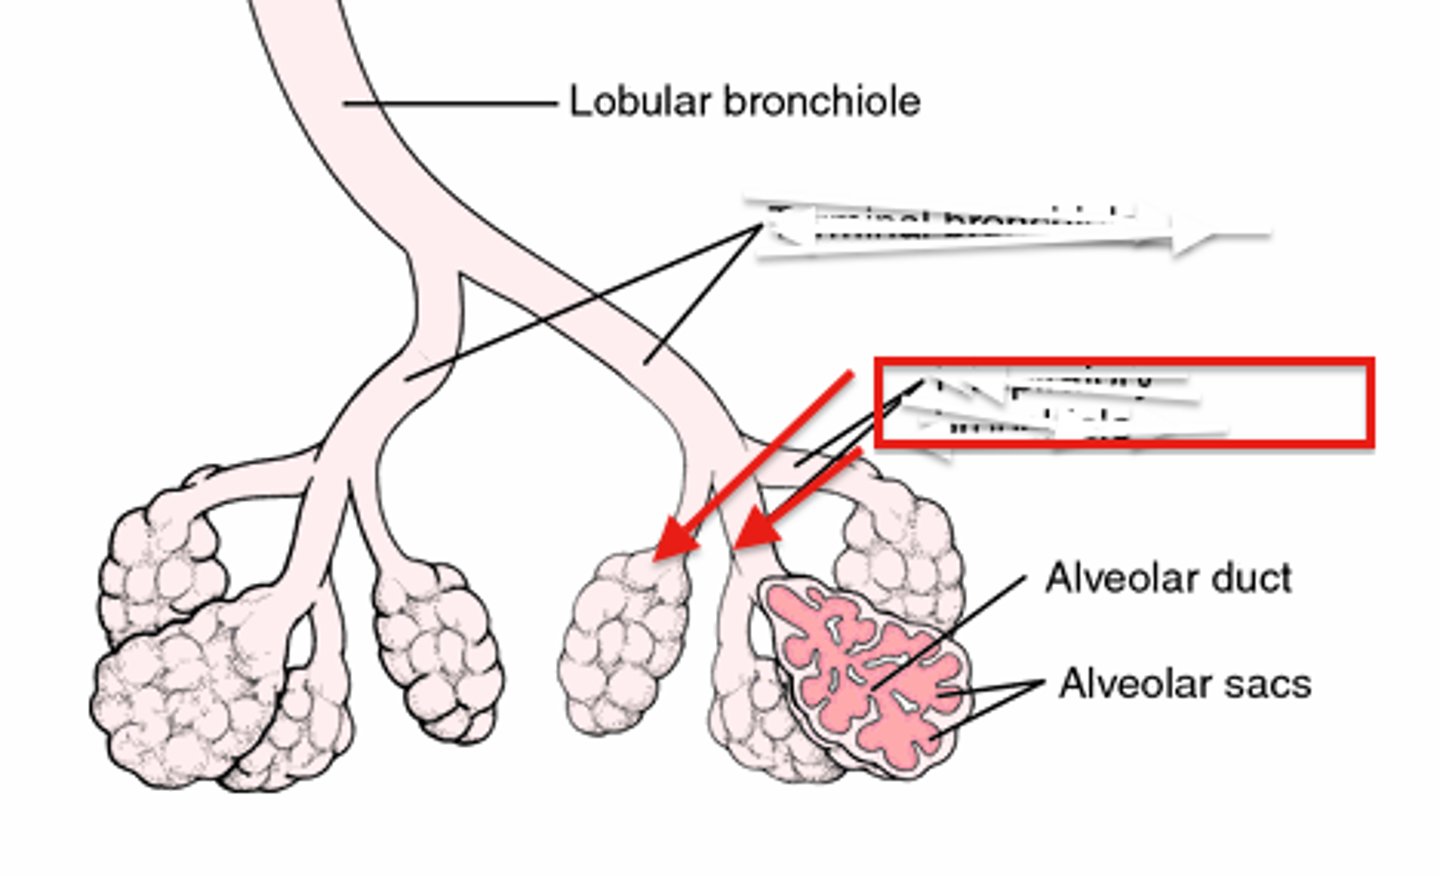

bronchiole

branch of bronchi that are 1 mm or less in diameter and terminate at alveolar sacs

respiratory bronchiole

branches of the terminal bronchioles that subdivide into several alveolar ducts

alveoli

tiny sacs of lung tissue specialized for the movement of gases between air and blood

alveolar ducts

Small passages connecting the respiratory bronchioles and the alveolar sacs.